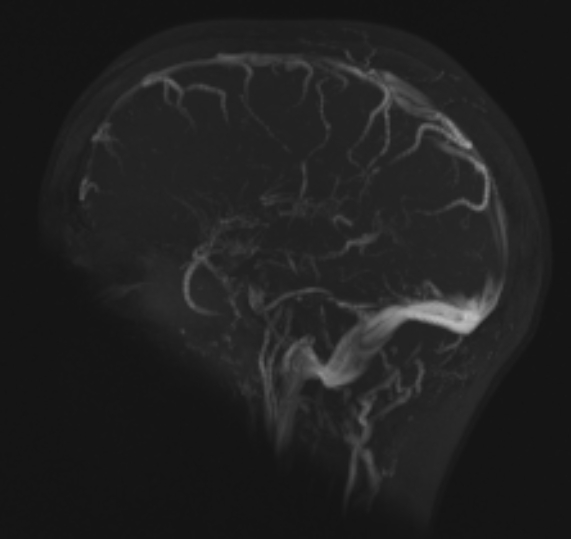

Cerebral vein thrombosis

MRI with sagittal vein cerebral vein thrombosis (notice lack of filling)